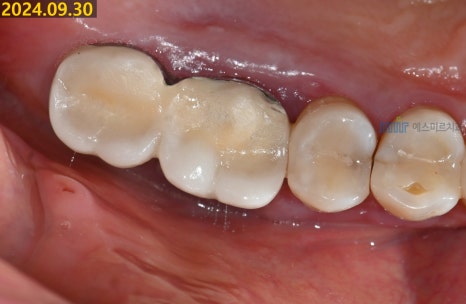

✨ 이번 치료는

염증이 있던 기존 임플란트를 제거하고,

뼈이식과 골유도 재생술을 동반한

임플란트 재식립까지

잘 마무리되었습니다.

(※ 환자 동의하에 제공된 이미지입니다)